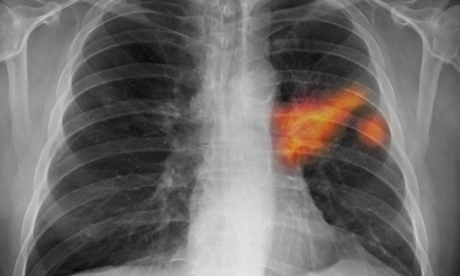

Lung cancer

AstraZeneca announced that it was bringing forward filing for approval for its lung cancer drug AZD9291. Photograph: Kallista Images/Visuals Unlimi

AstraZeneca is racing ahead with AZD9291, a lung cancer pill developed in the UK that is now due to be filed for approval in the second quarter of 2015, rather than in the second half of next year. Rival Clovis Oncology is developing a similar medicine. AstraZeneca, which faces patent expiries on several blockbuster drugs in the coming years, declared that cancer drugs would become its sixth growth platform, along with heart drug Brilinta, diabetes, respiratory, emerging markets and Japan. Biological medicines now account for nearly half the research pipeline.